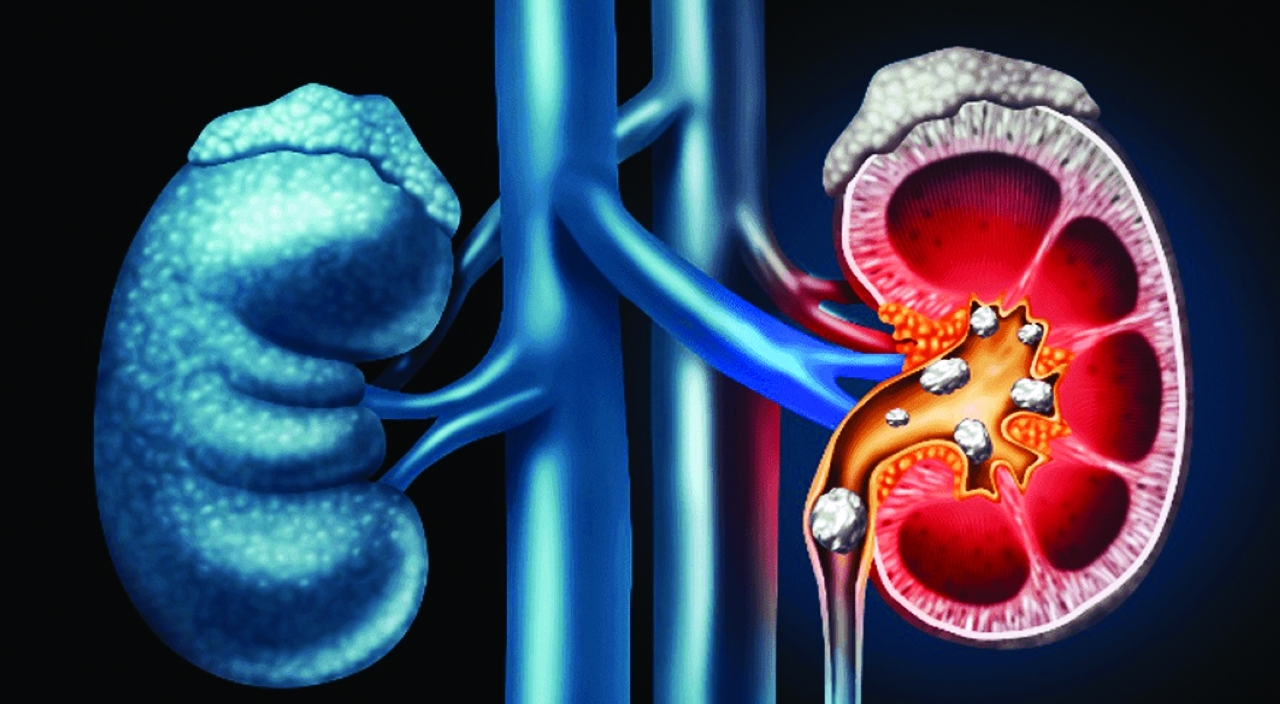

بحسب دراسة منشورة في صحيفة طب المسالك البولية في الولايات المتحدة، فإن تقنية علاجية جديدة صارت تتيح تفتيت الحصى في كلى الإنسان دون ألم. وتعتمد التقنية العلاجية الجديدة على إطلاق موجات فوق صوتية، من خلال تسليطها على الجلد حتى يذهب تأثيرها إلى داخل الكلية. وتستطيع الموجات أن تحدث تغييراً في تموضع الحصاة الموجودة في الكلية، حتى تصبح أكثر قدرة على أن تمر في المسلك وتخرج منه. ويؤدي وجود حصاة في جزء من الجهاز البولي يعرف بـ«الحالب»، إلى عرقلة مرور البول نحو المثانة لأجل التخلص منه، فيحصل الألم ويقع النزيف.

وتحل الطريقة الجديدة هذه المشكلة عبر طريقتين اثنتين؛ فإما إحداث تأثير لأجل تغيير تموضع الحصاة، حتى تتحرك، تمهيداً للتخلص منها. أما الثانية فهي تفتيت الحصاة إلى أجزاء قابلة لأن تخرج من المسالك البولية. وتتميزهذه التقنية الجديدة لأنها لا تسبب أي ألم تقريباً.